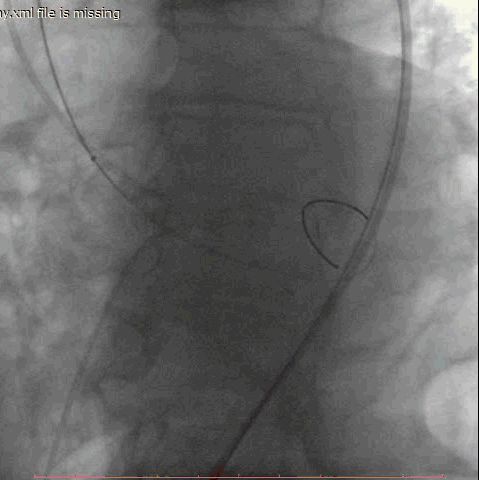

第一例手术的患者是一位86岁男性,间断胸闷症状2月,入院后超声提示主动脉瓣重度狭窄并少中量反流,平均跨瓣压差60mmHg,收缩期峰值流速4.9m/s,最大压差96mmHg。术前CT评估主动脉瓣环22.6*28.5mm,周长80.2mm,面积498.8mm2,右侧股动脉为主入路,应用24mm微创心通敖广球囊预扩张,植入27mm微创心通Vifaflow瓣膜,术后造影提示无瓣周漏,超声提示主动脉瓣跨瓣无压差。

术前影像